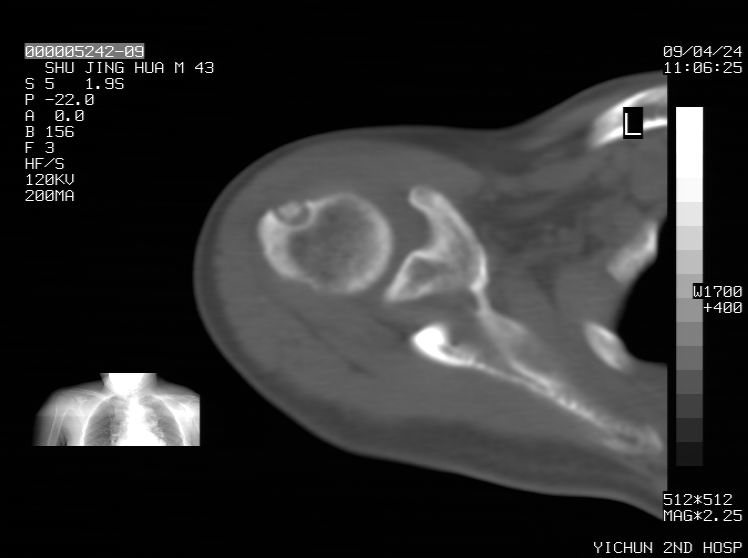

标题: CT19569:请会诊,女50岁,右肩疼痛数月 [打印本页]

标题: CT19569:请会诊,女50岁,右肩疼痛数月

骨软骨瘤?

考虑骨软骨瘤可能

剥脱性骨软骨炎